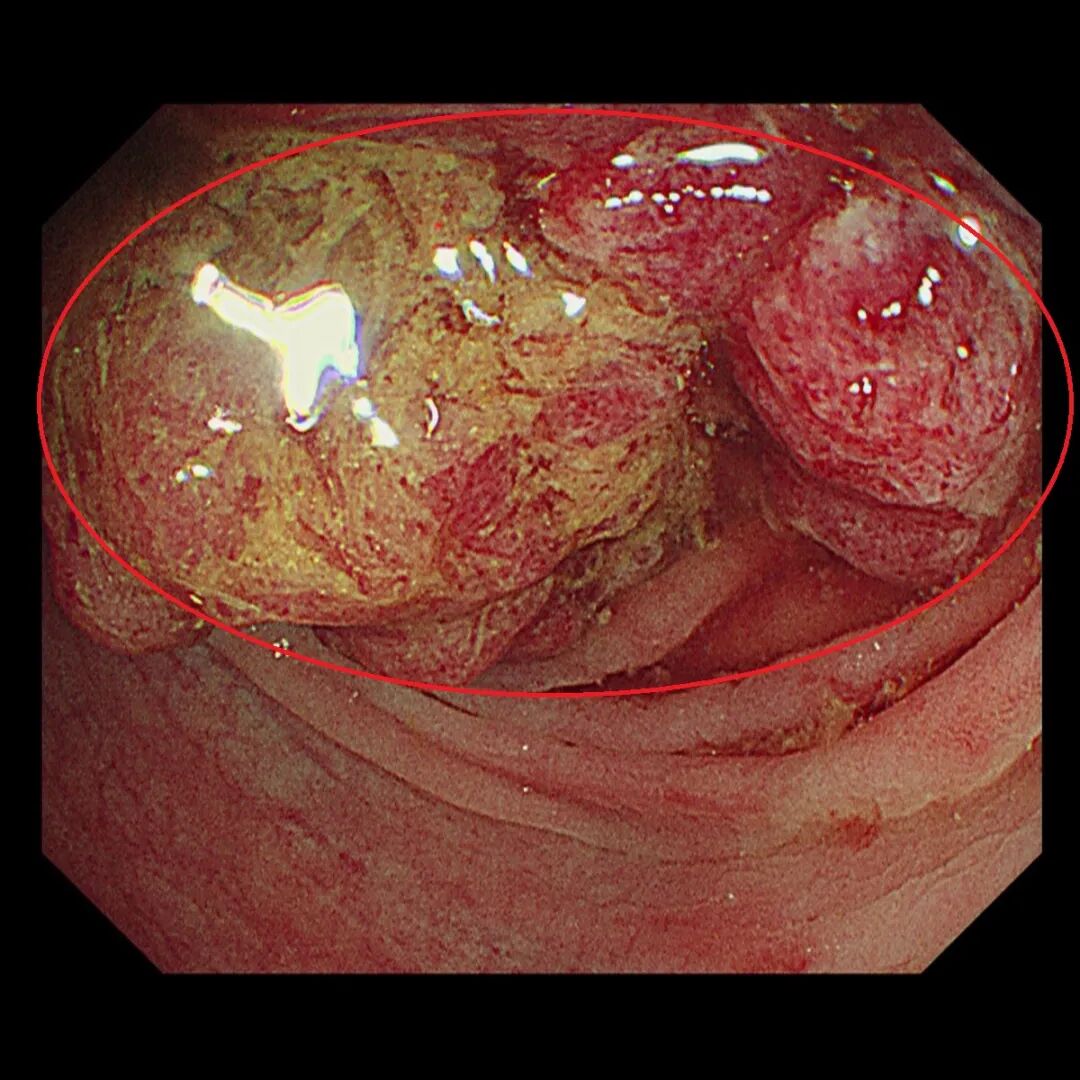

许多人直肠癌初期无感,等到排便总觉得排不干净,就诊后才发现有肿瘤。此图为直肠癌第 3 期,肿瘤已经占据直肠大部分空间。

直到第 3 期后,肿瘤不断刺激肠道,让患者常常急著解便,却总是觉得排不干净,而且次数越来越频繁。第 4 期是指癌细胞已经转移到身体其他器官。若患者未即时就医诊治,可能会出现便秘阻塞、骨盆疼痛以及直肠膀胱廔管,更甚者将面临死亡风险。